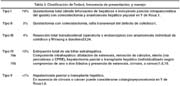

La clasificación aceptada actualmente es la propuesta por Todani en 19775. La variedad mas frecuente es el tipo I, o fusiforme, en el 79% de los casos, seguida por el tipo IV1 (tabla 3, figura 5). La distribución es similar en adultos y niños con excepción del tipo IV que es mas frecuente en adultos19,20.

El diagnóstico de quiste de colédoco durante la gestación o puerperio es raro. En la literatura se pueden encontrar los reportes de veintiún casos diagnosticados en la gestación y cuatro en el puerperio25-41. Entre los casos diagnosticados en la gestación trece se han presentado en el segundo trimestre y ocho en el tercero, y la mayoría han sido pacientes nulíparas. 75% de las pacientes manifi estan dolor abdominal, 50% ictericia, y 50% náuseas o vómitos. La mayoría han sido quistes de gran tamaño, entre 5x5cm y 20x20cm. El tipo Todani I ha estado presente en 82% de los casos. Una paciente tuvo desprendimiento de placenta, una tuvo preeclampsia, y dos tuvieron amenaza de parto prematuro. 14% de los casos terminaron con la pérdida del producto, 43% en parto por cesárea, y 43% en parto vaginal. Los abortos ocurrieron en pacientes con peritonitis biliar, colangitis, y sepsis postoperatoria25-41.